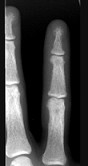

- 单项选择题女,41岁, 慢性肾功能衰竭,请结合图像, 选出最可能的诊断 ( )

B、甲状旁腺功能亢进